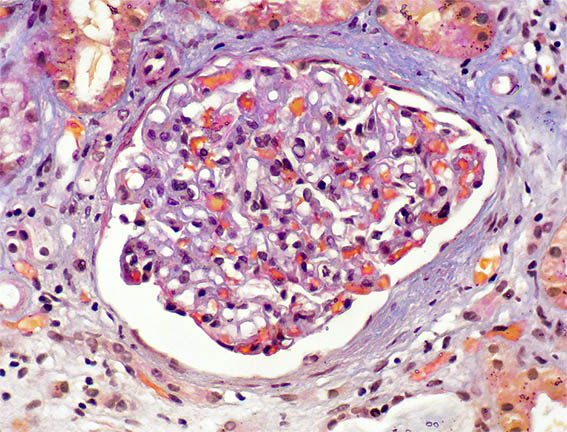

Figura 1. Tricrómico de Masson, X400. Glomérulos normales; hay fibrosis periglomerular.

Figura 2. Plata-metenamina, X400. Glomérulo con características normales.